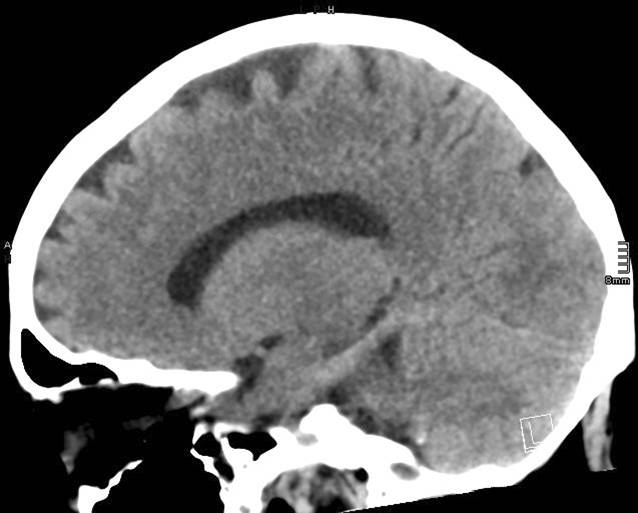

Für die Therapie der konvulsiven Anfälle wurden mehrere Substanzgruppen kombiniert. Die initiale Aufsättigung mittels Levetiracetam und Lacosamid in Kombination mit Benzodiazepinen (Midazolam, dann Lorazepam) sowie schließlich die Eskalation auf ein volatiles Anästhetikum (Sevofluran) über ein Anaesthetic Conserving Device [3] und die kontinuierliche Applikation von Propofol führten nicht zur Durchbrechung des Status epilepticus. Erst die zusätzliche Aufsättigung mit Phenytoin erzielte eine Reduzierung der epilepsietypischen Potenziale mit anschließender Burst-Suppression. Wegen des Verdachts auf eine Ureaplasmensepsis wurde am Tag 44 eine kalkulierte Antibiotikatherapie mit Ciprofloxacin und Clarithromycin begonnen. Noch bevor eine Nierenersatztherapie oder andere Maßnahmen zur Kontrolle des hohen Ammoniakspiegels initiiert werden konnten, waren die Pupillen der Patientin plötzlich nicht mehr lichtreagibel. Es wurde umgehend eine erneute kranielle Computertomographie durchgeführt, in der sich ein diffuses Hirnödem mit vollständig aufgehobener Mark-Rinden-Differenzierung sowie oberer und unterer Einklemmung zeigte (Abb. 4). Die Prognose wurde im Konsens der Behandler als infaust eingestuft. Die Patientin verstarb schließlich nach Verabschiedung durch die Angehörigen und Deeskalation der intensivmedizinischen Maßnahmen.

Abb. 4

Native kraniale Computertomographie, exemplarische Schichten einer sagittalen Rekonstruktion: diffuses globales Hirnödem mit Herniation der Kleinhirntonsillen als Zeichen der unteren Einklemmung, postoperativer Tag 44